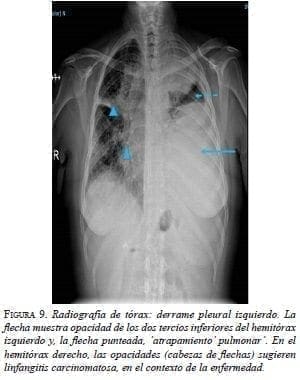

En la radiografía de tórax se observó derrame pleural izquierdo y aumento del tamaño de la silueta cardiomediastínica (figura 9).

En la TC de tórax se apreciaba derrame pericárdico, con tabiques, derrame pleural izquierdo, y engrosamiento pleural y pericárdico (figura 10).